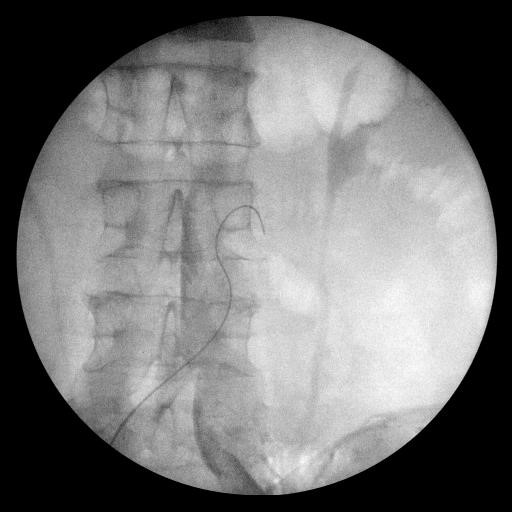

Киссинг  аорты и дополнительное  стентирование подвздошных артерий